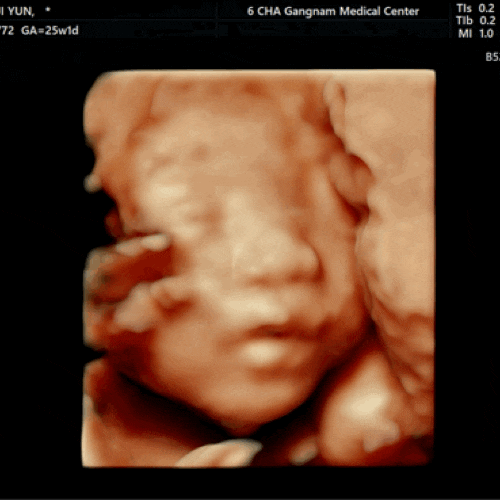

임신 25주 강남차병원 임당검사 시기 입체초음파 비용 및 후기 _깡깡이가 폴더로 접힌 사연

안녕하세요. 콩지입니다. 오늘은 드디어드디어 우리깡깡이 입체초음파 보고 임당검사까지 하는 날!! 떨려요...